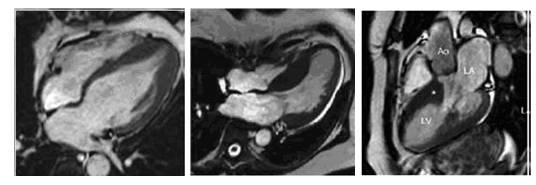

HOCM的超声诊断

◆CMR是目前最敏感、可靠的无创诊断方法。

我国2015年“心脏磁共振诊断心肌病”的专家共识建议以下情况推荐CMR检查:① 可疑HCM,超声诊断不明确时;② 可疑心尖部或侧壁肥厚以及非缺血性心尖室壁瘤的患者;③ 需进一步评估左心室结构(乳头肌病变等)以及心肌纤维化时;④ 与其他类型左心室肥厚表现心肌病(心肌淀粉样变等)的鉴别诊断;⑤ 室间隔化学消融及切除术术前指导与预后评估。

钆对比剂延迟强化(LGE)是目前临床评估心肌局灶纤维化最有效的方法,表现为肥厚心肌内局灶或斑片状强化。

2014ESC“指南”建议由心脏成像和心肌病检查经验丰富的团队进行 CMR 检查,对于无禁忌症且超声心动图声窗不足以诊断的疑似 HCM 患者,建议进行 LGE磁共振检查(I,B)。

HOCM的核磁诊断